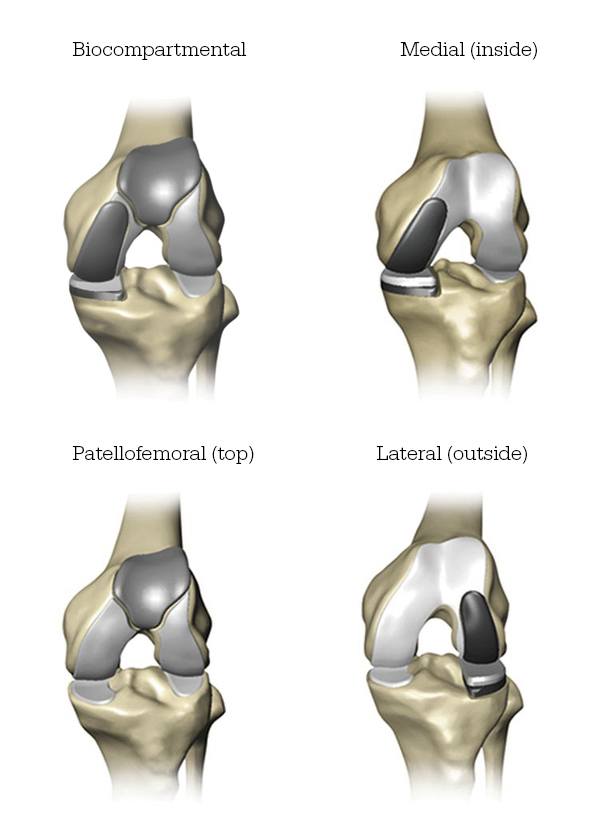

Mako Robotic-Arm Assisted partial knee replacement is a treatment option for adults living with early to mid-stage osteoarthritis (OA) that has not yet progressed to all three compartments of the knee. Depending on where the arthritis affects the knee, patients may have an implant inserted in any of the following areas: